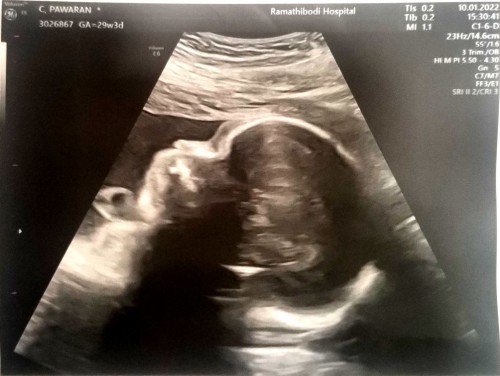

ลูกสาวแม่♥️

ดั้งหนูมาแล้วนะลูก👶 ตื่นเต้นทุกครั้งเลยค่ะ 25มีนานี้แล้ว แม่เห่อมากลูกสาวคนแรก🥰 แม่ๆคนไหนเตรียมของคลอดของใช้ อุปกรณ์ของเด็กอ่อน กันบ้างหรือยังคะ มาแชร์กันหน่อยนะคะ ตื่นเต้นไม่รู้จะทำอะไรก่อนเลยค่ะ#ขอคำแนะนำหน่อยค่ะ